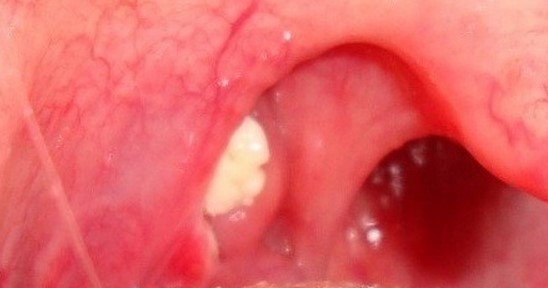

변도결석이란? ‘편’도선에 있는 작은 구멍에 하얗거나 노란색 이물질이 딱딱하게 생기는 것을 말합니다.

즉, 음식과 세균이 뭉쳐서 형성된 덩어리라고 할 수 있습니다.이 경우 양치질이나 양치질만으로는 입냄새를 없앨 수 없다고 합니다.편도결석 제거가 꼭 필요하거든요.